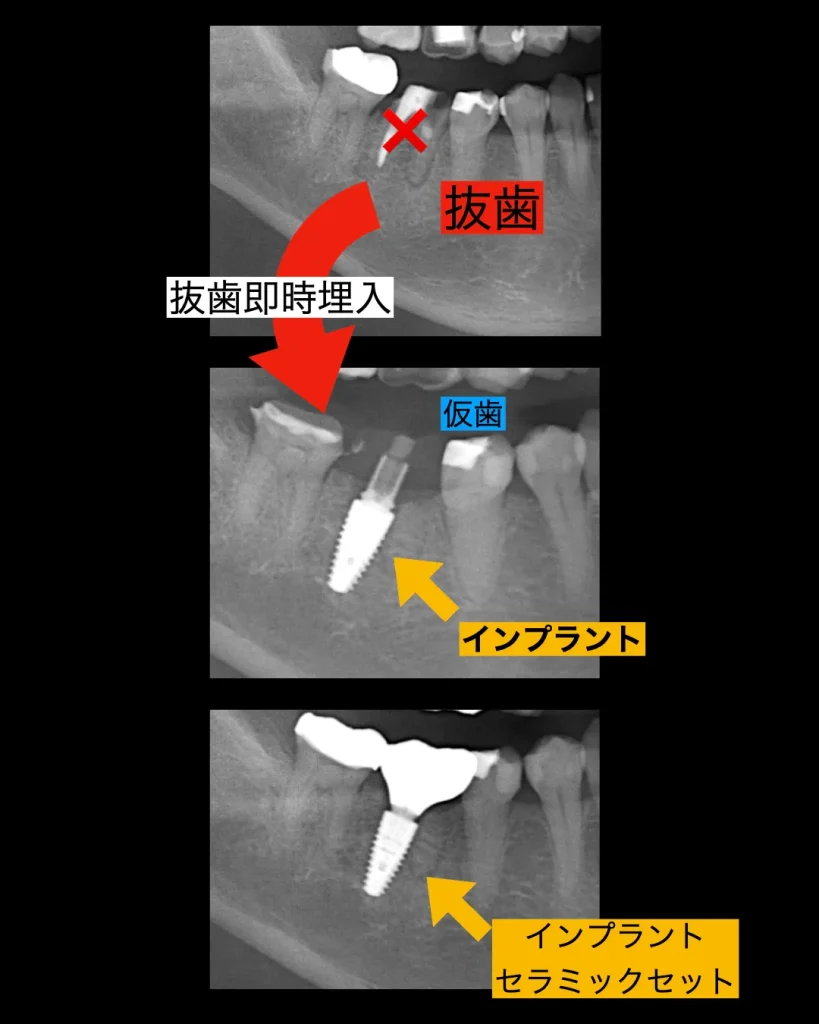

治療経過

治癒は良好で、3ヶ月ほどで仮歯の型取りを口腔内スキャナーで行い、噛めるようにしました。舌や頬を噛まない、問題なくしっかりと噛めることを確認した後、最終的なセラミックの上部構造をセットしました。

抜歯から3ヶ月で治療は終了しました。患者様は手術も1回で済み、痛みもほとんどなく大変喜ばれていました。今はメインテナンスに半年に1度、定期的に来院されており問題なくお食事を楽しまれています。何よりも喜ばれたのは手術が一回で済んだのと痛くなかったことだったそうです。